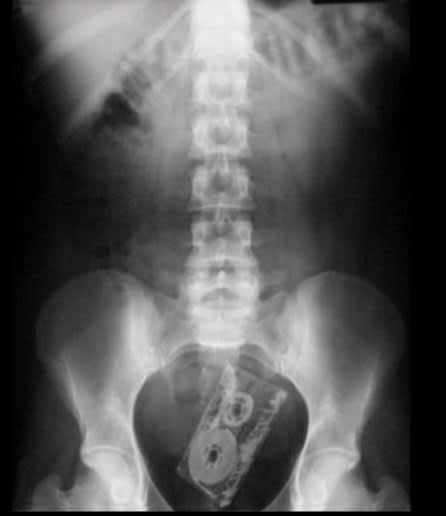

Petit jeu : le premier qui a trouvé l'ensemble des éléments coincés , a gagné 😊

la K7 c'est trop 80's la barbie aussi, non?

T'as triché . 😊Buzz l'éclair il était impossible à retrouver.

Un petit téléphone portable pour le plaisir :